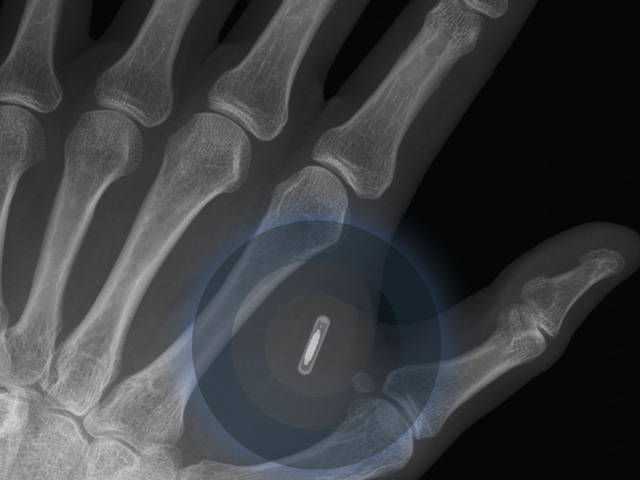

Năm 2025 – Điện thoại cấy ghép sẽ xuất hiện

80% các chuyên gia được hỏi đều dự đoán rằng trong 7 năm tới sẽ xuất hiện người đầu tiên được cấy ghép điện thoại di động vào cơ thể. Thiết bị này sẽ giúp theo dõi sức khỏe của người dùng một cách chính xác hơn so với những loại máy móc y tế hiện có. Đồng thời, người dùng có thể sử dụng điện thoại gấy ghép để giao tiếp với nhau bằng giọng nói hoặc sức mạnh tinh thần.